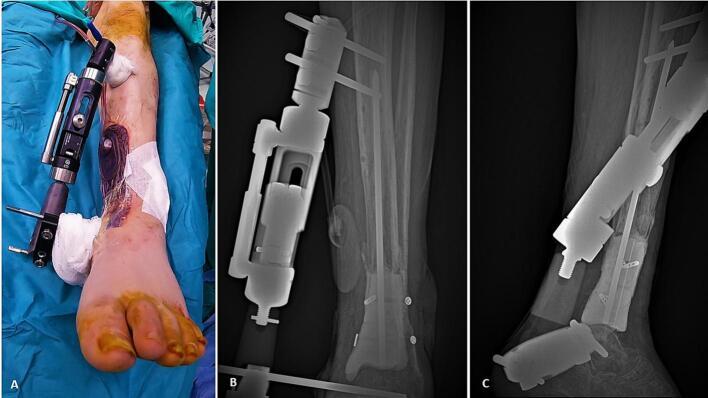

The management of septic non-unions with associated bone necrosis is challenging, especially when the resulting bone defect after the debridement is extensile. Different techniques have been described in the literature for the treatment of these demanding cases, with the most prominent being free vascularized Fibular graft and bone transport with distraction osteogenesis principles. Recently, 3D printing technology has been increasingly utilized in many complex orthopaedic pathologies. However, the application of those advancements regarding septic non-unions with residual bone defect has not been previously studied. This study presents a novel 3D printing technique for the management of an infected critical bone deficit of the tibia. Queries, challenges and future perspectives concerning the recruiting of 3D printing technology in limb reconstruction are also being discussed. Clinical Evidence Level: IV.

伴有骨坏死的感染性骨不连的治疗具有挑战性,尤其是清创后出现的骨缺损范围较大时。文献中描述了多种治疗这些复杂病例的技术,其中最突出的是游离带血管腓骨移植和采用牵张成骨原理的骨搬运。近年来,3D打印技术在许多复杂的骨科疾病中得到了越来越广泛的应用。然而,这些进展在伴有残余骨缺损的感染性骨不连中的应用尚未得到过研究。本研究提出了一种用于治疗胫骨感染性严重骨缺损的新型3D打印技术。同时也讨论了在肢体重建中引入3D打印技术的相关问题、挑战及未来展望。临床证据等级:IV级。